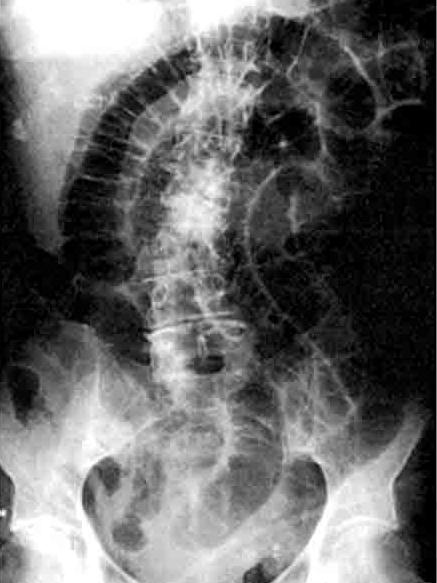

| Occlusion de l'intestin grele

avec image hydro-arerique du cadre intestinale est

en particuliairement que sa largeur est tres

etroite que la hauteur .et image de

transitionelle Region pelvienne est vite (

n'as pas de air intestinale ) . |

Image hydro -aerique en

escalier et sa largeur est tres etroite que la

hauteur . Occlusion de l'intestin grele , |